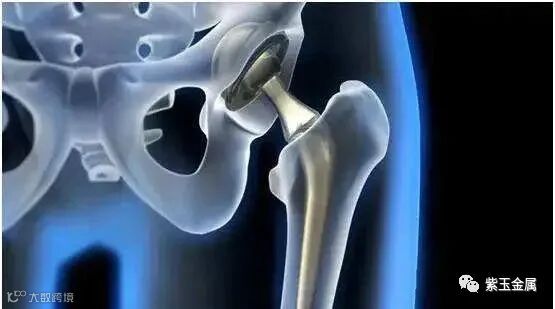

人工关节主要分为人工膝、髋、肘、肩、指、趾关节等,其中最主要的关节置换包括髋关节和膝关节,合计超过全球关节置换市场的95%。脊柱植入器械包括胸腰椎钉板系统,颈椎钉板系统和融合器系统等,其中椎间融合器系统主要用于椎间盘更换的治疗,也是最重要的细分领域,约占整个脊柱植入市场的一半。